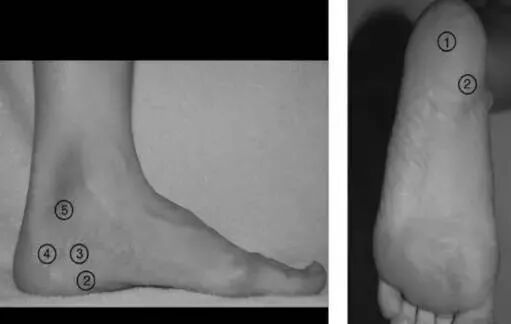

五种足跟痛的痛点及定位图1示:

图 1 五种足跟痛的压痛点和位置:①足跟垫萎缩 ②足底筋膜炎 ③巴克斯特神经卡压综合症 ④跟骨压缩性骨折 ⑤踝管综合症